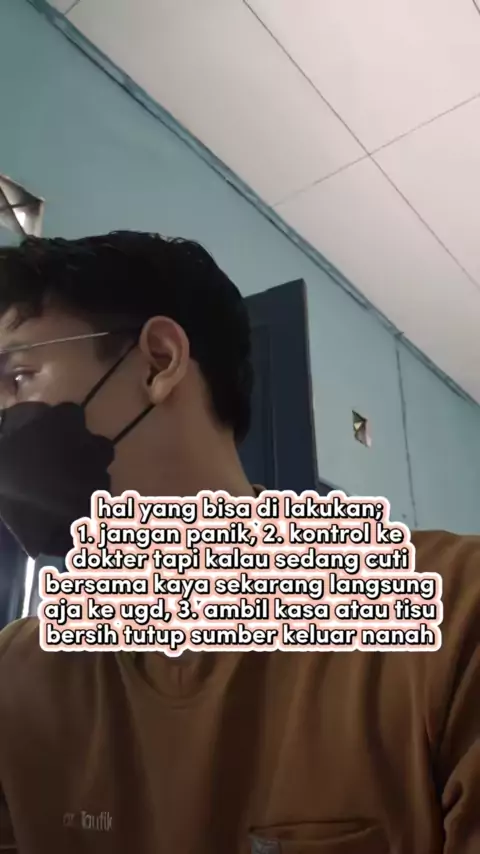

Membalas @bee.1219 mungkin hal ini yang bisa bunda lakukan kalau luka operasinya keluar nanah. #infeksilukaoperasi #ilo #Momsof #operasisesar #dokter